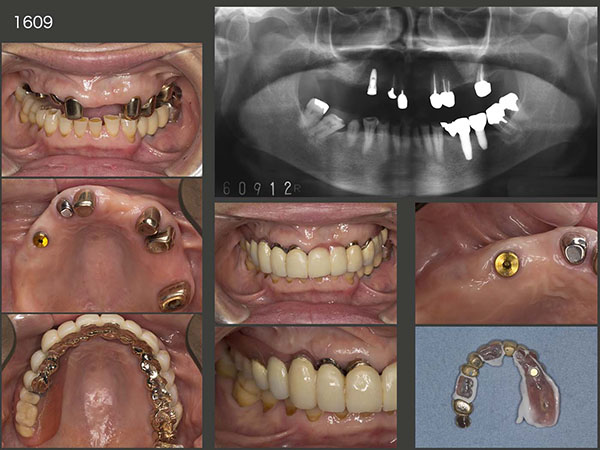

2003年12月初診の58歳女性.本格的な治療開始は,左下4の歯根破折による痛みが生じた06年3月から.まず,左下4を抜去し,当初はスライド下段に示すようなパーシャルデンチャーを8月に装着した.しかし,咬合面の金属色,左下3のクラスプの審美障害等から受け入れられず,結局インプラントを2本植立した.(06年9月オペ,07年5月補綴装置装着,スライド右下は07年11月,インプラント上部構造の咬合面は金属にして頂いた.)

その後の経過は,右側が咀嚼側になったためか,まず右上5が2013年4月に歯根破折した.続いて15年1月,右上3に歯根破折が生じた.右上3という防波堤を失ったため,直ぐに右上1,2もドミノ倒し的に歯根破折が生じると考えた.それを阻止する目的で15年9月,右上4部にインプラントを1本植立した.インプラントと骨が結合する待機中に,今度は右上2にフィステルが生じた.また歯根破折と考えたが,歯周ポケットが最大5mmであったことから,根尖病巣の再発あるいは歯根破折の両方が疑われた.根尖は大きく拡大していたため,通常の感染根管治療は無理と判断した.15年12月,この歯を抜歯してよく観察したところ,幸い破折線が認められなかったので,根尖病巣と診断し,通法にしたがって再植した.補綴装置は,歯になるべく側方力をかけたくなかったので根面板とした.

2019年2月に左上7を歯周病にて抜去した.4月,15年に再植した右上2および右上1にフィステルが出現したので,右上2については歯根端切除術,右上1については穿孔らしき部位をスーパーボンドにて閉鎖した.7月の時点では,フィステルは消失した.しかし,20年10月,右上2に再びフィステルが生じたため,今回はさすがに諦め抜去した.また左上4に歯根破折が生じ,抜去した.まだ支台歯が2本(右上1は危険な状態)とインプラントが1本あるので,義歯の安定は問題ない.しかし,総義歯に誘導するか,左側にもう1本インプラントを追加するかの判断をする時期は近い.(私は,総義歯で十分と思われるが,最終的には口蓋義歯床の違和感を患者さんがどの程度訴えてくるかによる.)